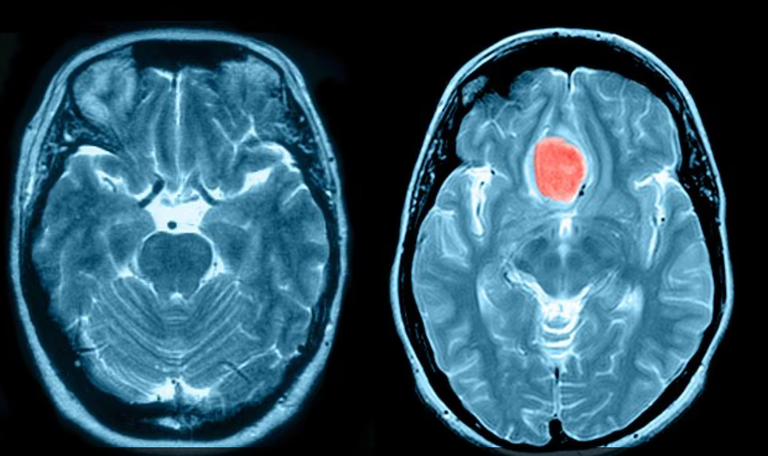

كانت كلير، 41 عاما، تعمل كمساعدة في مدرسة لذوي الاحتياجات الخاصة، تستيقظ ليلا بشكل متكرر تعاني من صداع، لكنها ظنت في البداية أن السبب هو الإجهاد الناتج عن مسؤولياتها كأم لطفلين من ذوي الاحتياجات الخاصة. وبعد ستة أشهر من تجاهل الأعراض، زارت طبيبها العام بناء على إلحاح زوجها، لتكتشف لاحقا إصابتها بـ"الورم السحائي" (Meningioma)، وهو أكثر أنواع أورام الدماغ شيوعاً.

يُعد الورم السحائي عادة بطيء النمو وغير سرطاني، لكنه يمكن أن يسبب مضاعفات خطيرة في حال ترك دون علاج، مثل فقدان البصر، وتغيرات في الشخصية، وفقدان الذاكرة، وحتى الشلل. وتحدث هذه الأورام عادةً لدى الأشخاص فوق سن الـ60، ما جعل تشخيص كلير في سن 35 أمراً غير معتاد.